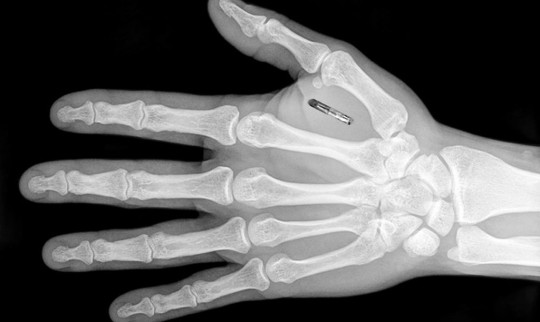

Микрочиповете, които са големи колкото зърно от ориз, струват по 150 паунда всеки.

Те се поставят в кожата между палеца и показалеца и могат да се използват като всякакъв вид предавател - например за отваряне на врати. Те също така могат да бъдат натоварени с медицински данни, до които може да има достъп, ако лицето претърпи инцидент.